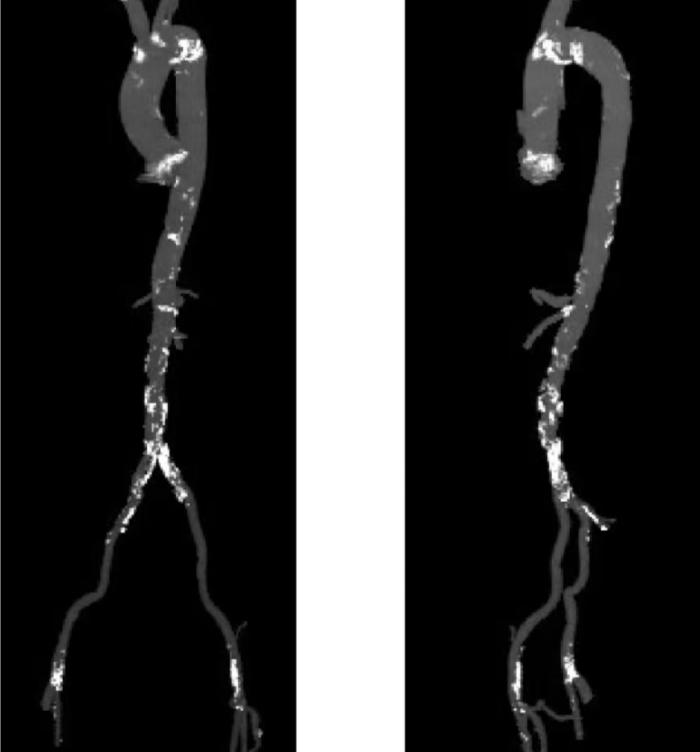

今年73岁的李先生(化名),因反复胸痛、气促入院,活动能力明显受限。经全面检查,发现其病情极为复杂棘手。作为心脏“输水管道”的冠状动脉主干及多支血管存在多处严重狭窄,心肌供血严重不足;被称为“心脏大门”的主动脉瓣重度钙化、狭窄,已引发心功能衰竭;而作为手术器械输送“生命通道”的外周血管,同样存在严重钙化、溃疡与狭窄。这三种病变单独存在均足以危及生命,叠加后使传统外科开胸手术风险陡增,患者一度面临治疗困境。

手术过程犹如在心脏内进行的“微雕”和“换门”工程,步骤环环相扣,每一步都考验着术者的技术功底与团队协作默契。术中,团队首先利用先进的可扩张血管鞘,在严重钙化狭窄的右侧股动脉腔内成功建立安全的手术通路;随后经该微创入路,先通过球囊扩张术为冠状动脉植入支架,快速恢复心肌血供;紧接着,在同一手术台、同一入路下,精准将人工主动脉瓣输送至病变位置并成功释放,顺利替换失灵的原生瓣膜。整个过程中,团队成功克服了外周血管入路困难的核心挑战,确保手术各环节无缝衔接、精准落地。

术后,患者主动脉瓣功能即刻恢复正常,冠状动脉血流重回通畅,胸闷、气促等不适症状显著缓解。经过后续康复护理,患者已顺利出院,重获正常生活能力。